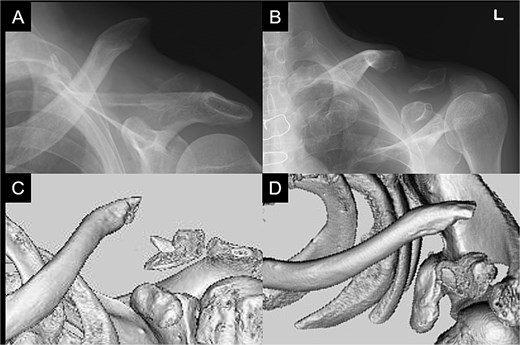

A 66-year-old man presented with left shoulder pain after falling. A Neer Type IIB fracture of the distal clavicle with significant displacement was revealed on radiographs (Fig. 1); however, owing to severe aortic valve stenosis and heart failure, the patient was deemed unfit for surgery. The patient underwent conservative treatment for distal clavicle fracture for 5 months; however, the pain in the left shoulder persisted, and significant skin protrusion caused by a displaced bone fragment was noted. No findings suggestive of neurovascular injury were observed. Radiography and computed tomography (CT) examinations revealed fracture displacement progression (Fig. 2A–C). After undergoing aortic valve replacement 3 months postinjury, the cardiac function of the patient improved and surgery was performed to treat the distal clavicle nonunion.

Radiographs (A and B) and CT scans (C and D) captured after 5 months of conservative treatment show that the displacement has progressed.